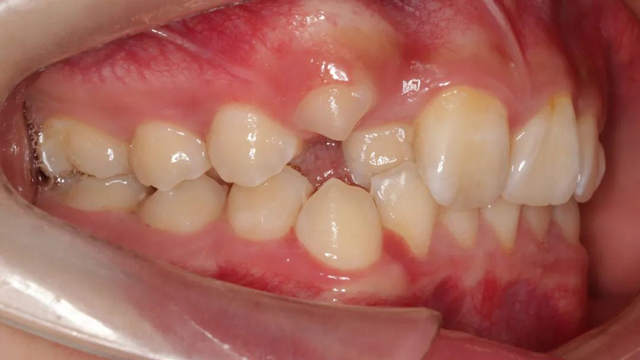

2021年8月(矫正前口内照)

这位小患者的口腔问题包括:牙列不齐,个别门牙反颌,左上尖牙完全埋伏阻生,另外,CBCT显示右上门牙牙根腭侧内还有一颗多生牙。

简单地说,牙齿不整齐只是小问题,他更大的问题是:在不该长牙的地方多长了一颗牙,而乳尖牙滞留,早该替换出来的尖牙长不出来,这两颗牙的问题如果不及时干预治疗,会带来很多长期的口腔问题。